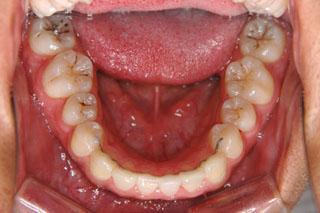

2年半ほどの治療で、装置を撤去し保定治療に移行しています。飛び出ていた前歯も、下の歯と正しく噛めるようになりました。口元の突出も消え、口唇閉鎖時に前歯が覗いて見えるという事も無くなりました。

保定治療に移行してから3年半が経過しました。上の顎に生えてきた親不知は下の顎の奥歯と噛み合うようになりましたが、下の親不知は、斜めに埋まっていましたので、噛み合わせへの変化を防止するためにも早めに抜いて貰いました。矯正治療ではなるべく長期に渡って、管理を行いますが、2年3年と大きな変化が無く、緊密な噛み合わせが確保出来ていれば、将来的にも安定が期待出来ると思います。